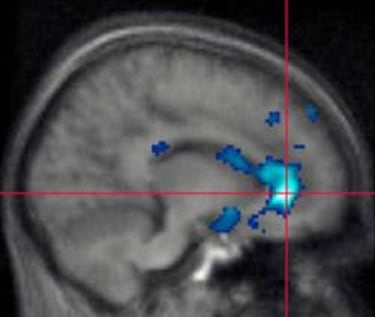

El martes un investigador de la Michigan State University y sus colegas presentaron un estudio en el que aseguran que han demostrado que al jugar con videojuegos violentos la actividad en el cerebro es comparable a la que ocurre cuando se tienen pensamientos agresivos. El estudio se llevó a cabo sometiendo a 13 hombres a resonancia magnética funcional mientras jugaban con un videojuego violento. Posteriormente se analizaron todas las imágenes de las resonancias. René Weber, de la MSU, dirigió la investigación y colaboraron con él Klaus Mathiak, de la Universidad RWTH de Alemania, y Ute Ritterfeld de la Universidad del Sur de California.

La resonancia magnética funcional permite detectar las zonas del cerebro que se activan en determinadas actividades y sensaciones físicas. Los 13 hombres que participaron en el proyecto tenían entre 18 y 26 años, jugaban con videojuegos una media de 15 horas por semana y empezaron a jugar desde los 12 años de media. De los 13 participantes, 11 mostraron efectos evidentes en su cerebro provocados por la violencia virtual. Para los más curiosos diremos que el juego elegido fue Tactical Ops: Assault on Terror.